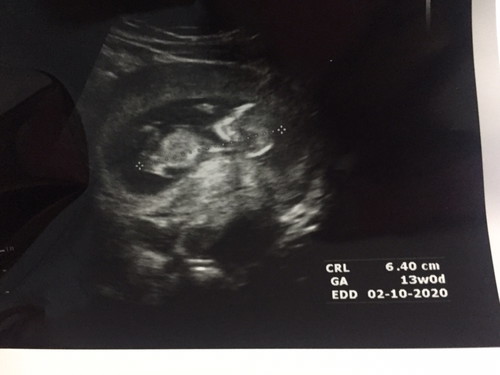

อัลตร้าซาวน์ 13 สัปดาห์

ขอดูภาพอัลตราซาวน์น้อง 13 สัปดาห์ของแม่ๆหน่อยค่ะ น้องมีขนาดเท่าไหร่กันบ้าง

อันนี้ตอน 12+6 จ้า